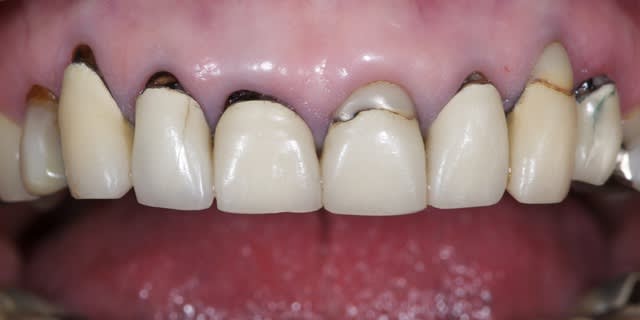

La demande concerne la réhabilitation esthétique du bloc incisif supérieur.

Bin! Y'a pas grand chose à dire en faite. Suffit d'appliquer quelques dogmes d'esthétique du sourire( voir ouvrage de J.C. PARIS du même nom). Donc on simule la ligne des bords libre en fonction de la lèvre inf lors du sourire, on s'occupe de l'esthétique rose en fonction du sourire, et là l'intérêt d'un conjonctif enfouie sur 13 et 23 est discutable car la patiente ne semble pas les découvrir lors du sourire, par contre une élongation de 11 et 21 (si leur longueur le permet: racine courte), serait la bien venue afin d'harmoniser les formes des futur couronnes . Enfin on zieute du coté des couloirs vestibulaire et on remarque qu'une réhabilitation de 14 à 24 ne sera pas suffisante pour redonner toute sa splendeur à ce sourire: de 6 à 6 semble bien mieux indiqué.

évidement ça fini en recouvrement périphérique pour tout le monde avec de la jolie céramique pleine de vie et de naturelle.

La suite avec les deuxièmes provisoires en places, le projet esthétique étant validé, les emp. ont été réalisées, ceramo-metal sur moignon composite a venir..